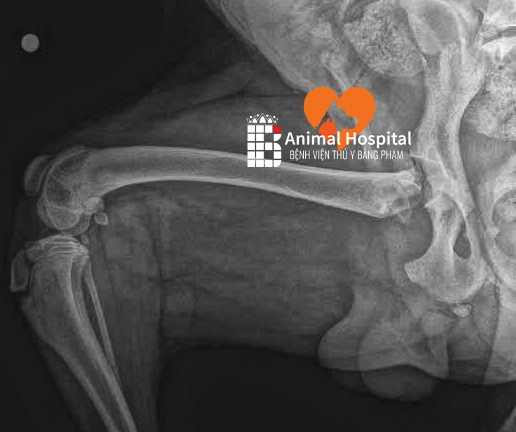

Tại đây, kết quả chụp X-quang cho thấy Nâu bị tổn thương cực kỳ nặng tại khớp háng. Về mặt giải phẫu, khớp háng có cấu trúc “khối cầu – ổ cối” kết nối xương chậu và xương đùi, đóng vai trò thiết yếu giúp khớp linh hoạt ở nhiều góc độ để thực hiện các hoạt động đi lại, chạy nhảy và giữ thăng bằng.

Cú ngã đập mạnh xuống nền đường cứng đã tác động trực tiếp vào vùng mấu chuyển lớn của bé. Hậu quả là Nâu bị gãy ở cổ xương đùi, tức là vị trí nằm ngay giữa chỏm và khối mấu chuyển của xương đùi. Đây là một dạng chấn thương rất phức tạp.